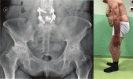

Preoperative planning is mandatory to achieve the restoration of a correct and personalized biomechanics of the hip.The radiographic review is the first and fundamental step in the planning. Limb or pelvis malpositioning during the review results in mislead planning.Correct templating is possible using three different methods: acetate templating on digital X-ray, digital 2D templating on digital X-ray and 3D digital templating on CT scan.Time efficiency, costs, reproducibility and accuracy must be considered when comparing different templating methods. Based on these parameters, acetate templating should not be abandoned; digital templating allows a permanent record of planning and can be electronically viewed by different members of surgical team; 3D templating is intrinsically more accurate. There is no evidence in the few recently published studies that 3D templating impacts positively on clinical outcomes except in difficult cases.The transverse acetabular ligament (TAL) is a reliable intraoperative soft tissue reference to set cup position.Spine-hip relations in osteoarthritic patients undergoing hip joint replacement must be considered. Cite this article: EFORT Open Rev 2019;4:626-632. DOI: 10.1302/2058-5241.4.180075.